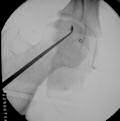

Kalça artroskopisi açık cerrahi prosedürlere göre daha güvenli olup hastaların daha erken iyileşme ve normal hayata dönüşünü sağlar. Açık cerrahi kıyasla komplikasyon (beklenmeyen sorunlar) daha nadir görülür. Yine açık cerrahiye oranla, hastanede kalış süresi ve işe dönüş süresi daha kısadır. Ameliyatta genelde 2 veya 3 cilt kesisi yapılır...